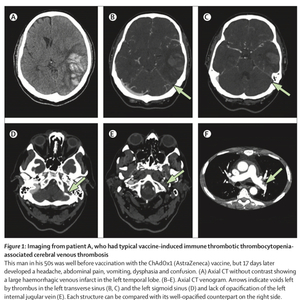

研究也发现,与非VITT脑静脉血栓形成患者相比,VITT相关患者有分布更广的静脉血栓,多发性脑梗塞、多发性脑内出血和颅外血栓的比例也更高。VITT相关患者在第一次静脉造影中静脉血栓数量(中位数3,IQR 2-4)高于非VITT组(2,2-3;p=0.041)。入院时的神经影像学检查结果显示,VITT患者(14%)比非VITT患者(0)更有可能出现多发性静脉梗塞,也更有可能出现多发性脑内出血(33% vs. 12%)。